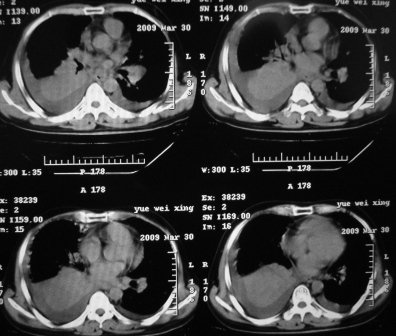

xx 男 43岁

右肺下叶支气管中断闭塞,右下肺见不规块影,并胸腔积液,考虑肺中央型肺癌继发下叶不张,\\双侧胸腔积液,心包积液。

考虑右中央型肺癌并下叶不张,双侧胸腔积液,心包积液

右侧中央型肺癌伴右肺下叶不张,双肺及纵隔淋巴转移,双侧胸腔积液,心包积液。

1)考虑右侧中央型肺癌伴右肺下叶不张,双肺及纵隔淋巴转移。2)双侧胸腔积液,以右侧为甚。3)心包积液。

考虑右肺下叶中心性肺癌并纵隔淋巴结、双肺转移伴右肺下叶阻塞性肺不张;双侧胸水,右侧为著;心包积液